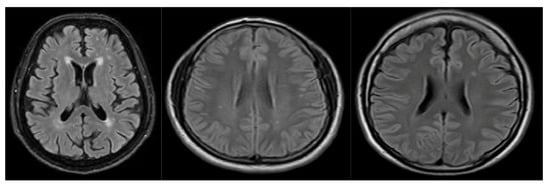

3.1. Dataset

3.1.1. Analysis of Volumes and Slices Dataset

- The variability of the public data, in the sense that it was acquired from different equipment, may introduce bias, affecting model performance. Another limitation with respect to the data is that the private dataset is built with the annotation of experts by only one health institution; according to the literature, together with the artifacts and the noise produced with the equipment, the annotations also depend on the physician’s expertise.